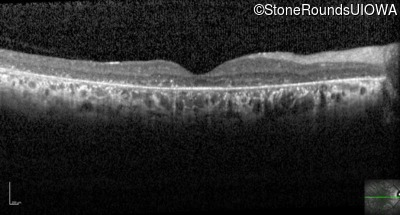

Optical Coherence Tomography - Right - 20/150 sc

Exemplar / OCT Stack

OCT Stack